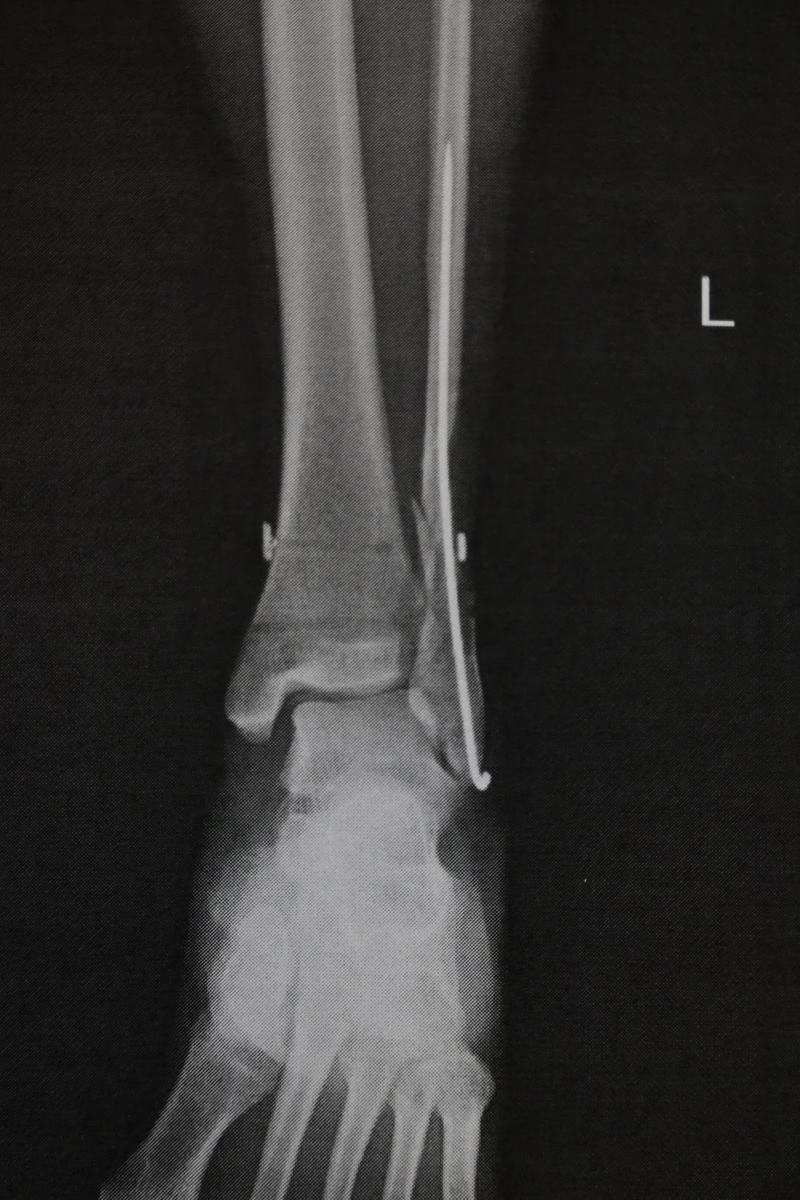

一昨日深夜の手術終了時に手術したお医者さんに藁半紙でX線写真をもらいました。

紙を撮影してるので意味ありませんが

腓骨の中に金属棒を入れての処置になったそうです。プレートでの固定は切開部が大きく術後の痛みが大きい、プレート取り外し時の入院が長くなるので金属棒でよかったです。

横に見える貫通穴は筋が切断したので人工のものを設置した穴です。

もう一か所、縫い合わせた筋がありますが画像で確認できません。

結論として切開が少なくピン抜きも楽な形にまとめてもらいました。切開部分が多いと手術後の痛みが激しいので切開が少なくてよかったです。